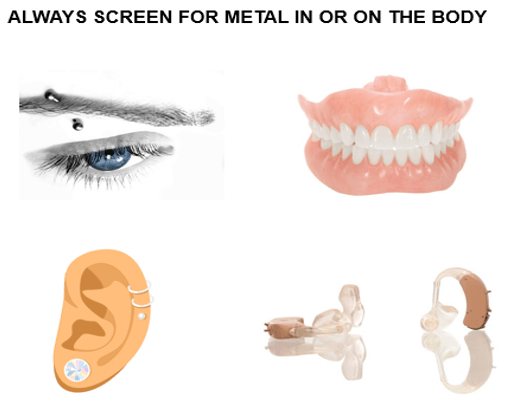

Patient Education

Patient education helps to ensure a quality examination. It is important to inform the patient to lie still during the scan and make them aware of the breathing requirements ahead of scanning. Remember to always screen for the metal in the body to prevent image artifacts. Metal includes hearing aids, body piercings and also dentures that are removable. For their comfort, it is also important to remind them you can see them at all times during the exam.